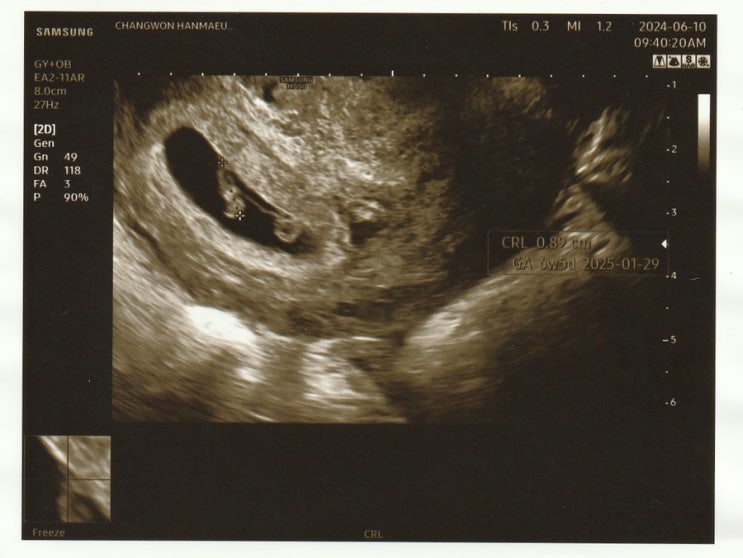

임신 6w5d / 태아 심장소리 / 창원한마음병원

2024. 06. 10 (월) 8시 채혈 9시 15분 진료 예약 9시 40분 진료 8시에 병원 도착하자마자 1층에 채혈하러 ...